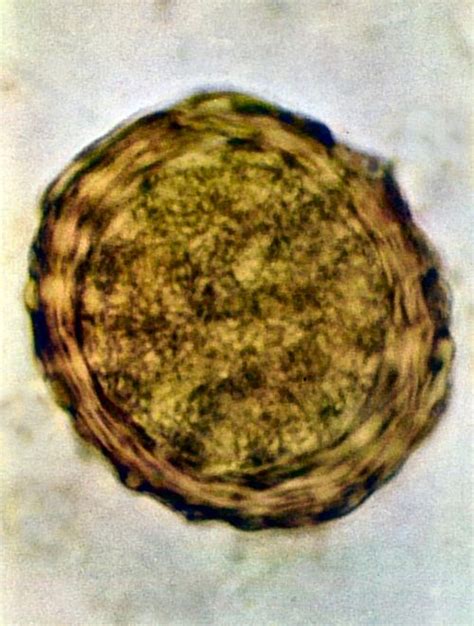

Diagnostika kožnej mykózy zvyčajne zahŕňa klinické vyšetrenie a odber vzoriek postihnutej kože alebo nechtov. Laboratórne testy, ako sú kultivácia alebo mikroskopické vyšetrenie, pomáhajú identifikovať konkrétny druh huby. Táto metóda umožňuje identifikovať konkrétny druh huby. Môžu sa tiež vyšetriť hladiny protilátok proti konkrétnym druhom plesní a kvasiniek.